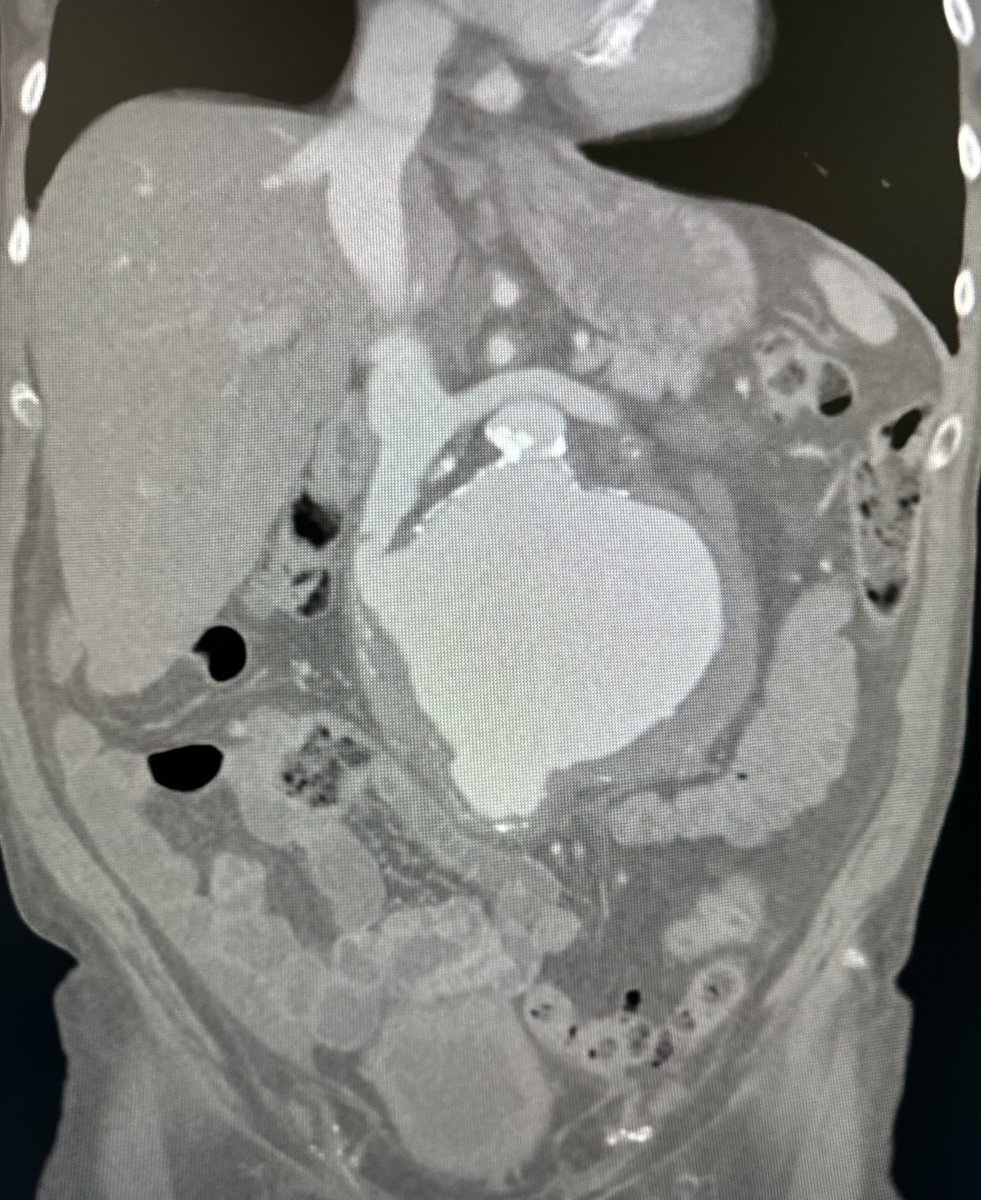

6 pack aorta?! Omentum gone from prior colonic resection after ischemic colitis…referred for an infected ABFB. Bilateral rectus abdominis flaps used to assist in coverage of rifampin soaked graft. @uazphxsurgery